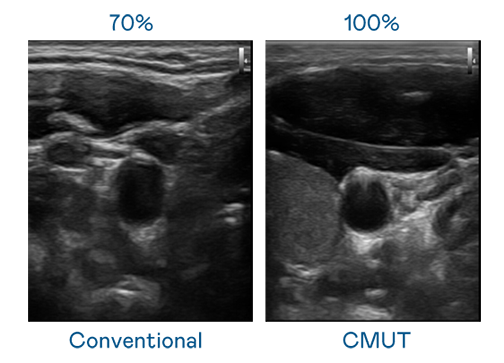

CMUT 技术是一种用电容式微机电元件来产生超音波讯号的技术。与传统 PZT 压电式技术相比,CMUT 频宽增加 30%,更宽频的超音波讯号让影像解析度大幅提升,是实现高影像品质医疗超音波扫描、促进精准医疗发展的关键技术。

超音波影像的解析度高低,首先取决于探头能发出的讯号频宽。后宫露营 CMUT 可提供高清晰的超音波讯号,提供高频宽、高灵敏度、影像纹理细节更高的超音波影像,协助医护人员缩短影像判读时间及利用精准的医疗影像进行诊断。